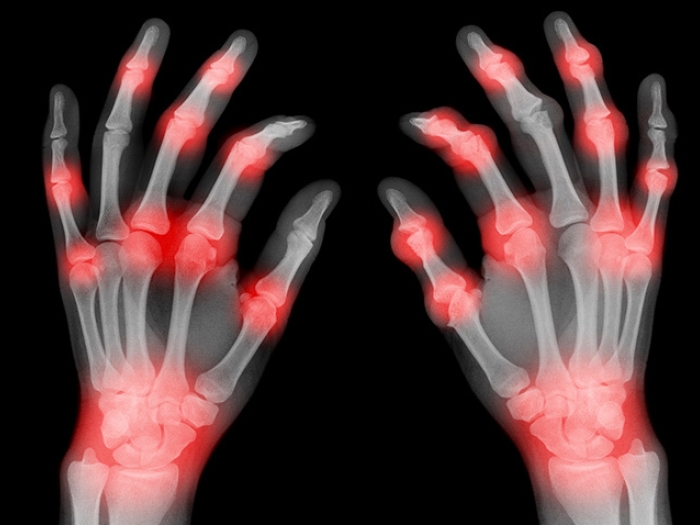

hands of xray finfers with red spots

How to live pain-free with arthritis

Arthritis of the hands, wrist and fingers can be unbearable, but a doctor says you don’t have to live in agony.